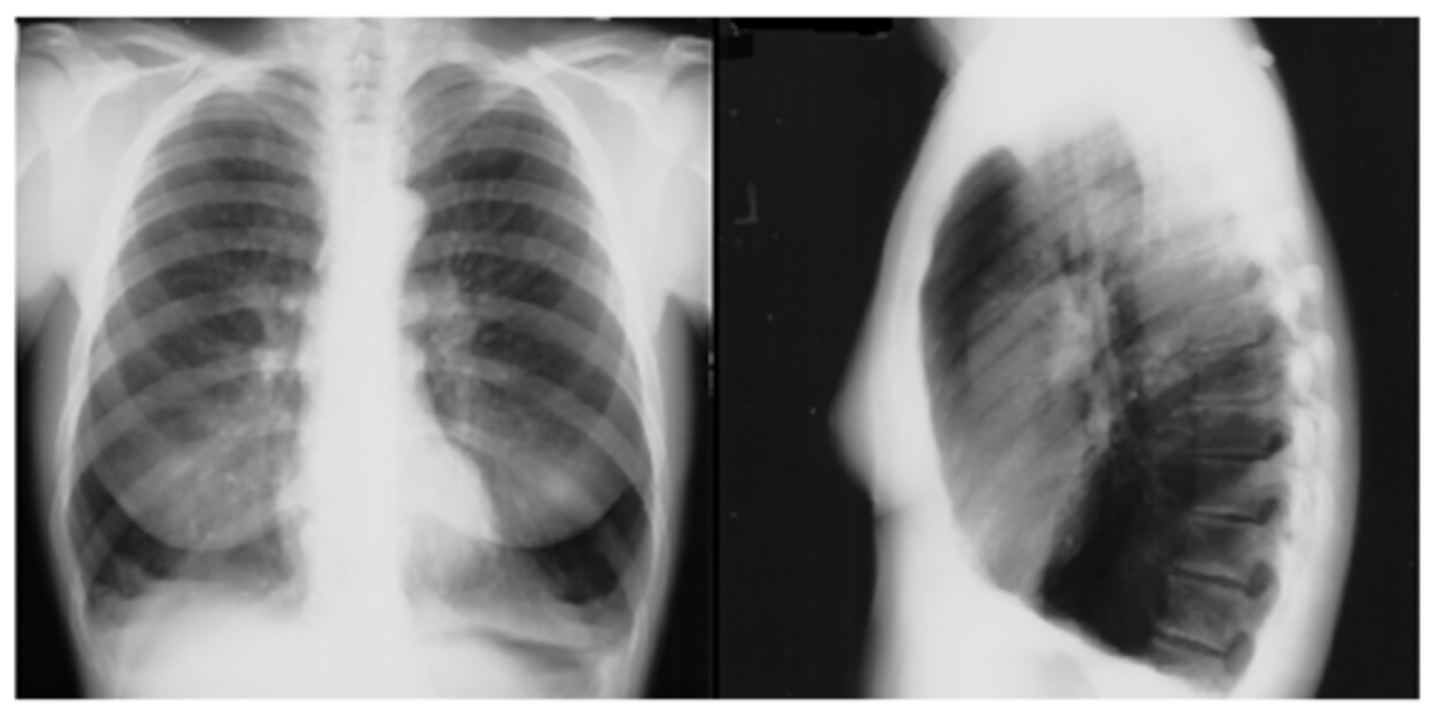

complete or partial collapse of the entire lung or area (lobe) of the lung. It occurs when the tiny air sacs (alveoli) within the lung become deflated or possibly filled with alveolar fluid

atelectasis - R lung collapse

--note: collpased lung pulling mediastinum towards R

Dx